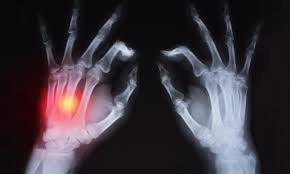

류마티스 관절염은 만성 염증성 자가 면역 질환으로

관절에 영향을 끼치고 신체 다른 부위에도

영향을 미칠 수 있다.

이것은 활막(관절을 감싸는 막)의 염증 때문이다.

이 활막의 두께가 두꺼워지기 시작하고

염증이 생긴 세포가 뼈와 연골을 소화하는 효소를

방출함에 따라

관절 손상 및 기형을 유발할 수 있다.

1. 손과 손목

일반적으로 손가락, 손목의 작은 관절에서 시작됨.

X- 레이에서 볼 수있는 관절 침식은 관절 이동성 및 기능의 제한과 관련이 있습니다. 도 9는 공동이 침식되고 연골이 손상되기 때문에, 뼈의 뼈 접촉은 통증 최종 결과 일 수 있다.

연골, 힘줄, 인대 및 뼈의 심각한 손상은 관절을 불안정하게 만들 수 있습니다. 관절 불안정성은 아 탈구 또는 덜 자주 탈구로 이어질 수 있습니다 .